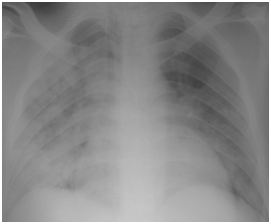

Figure 4E Follow up Chest x-ray showing further improvement.

Figure 4F Follow up chest X-ray 4 days after the end of H1N1 therapy.

Figure 4 H1N1 radiological pictures in a diabetic 28-year-old transplant recipient.

H1N1 infection in RTR can result in many morbidities and mortalities however early clinical suspicion and starting oseltamivir immediately upon clinical suspicion is to decrease the morbidity and mortality. Doubling the dose, extension of duration of treatment and reduction of immunosuppressive drugs (when indicated) are the keys for successful management of H1N1 infection in RTR. Diarrhea should be stressed upon diagnosis of H1N1; also admission of these RTR is critical because diarrhea can complicate RTR with severe decompensate metabolic acidosis and severe dehydration. Marvelous clinical response to oseltamivir therapy in established cases of pneumonia can be followed up radiologically by serial CXR while CT is important in diagnosis of suspected cases of pneumonia without conclusive CXR. The time incidence of H1N1 varies according to geographic distribution, however any RTR with flu symptoms in any time in the year should be suspected for H1N1 and treated immediately to obtain better prognosis.